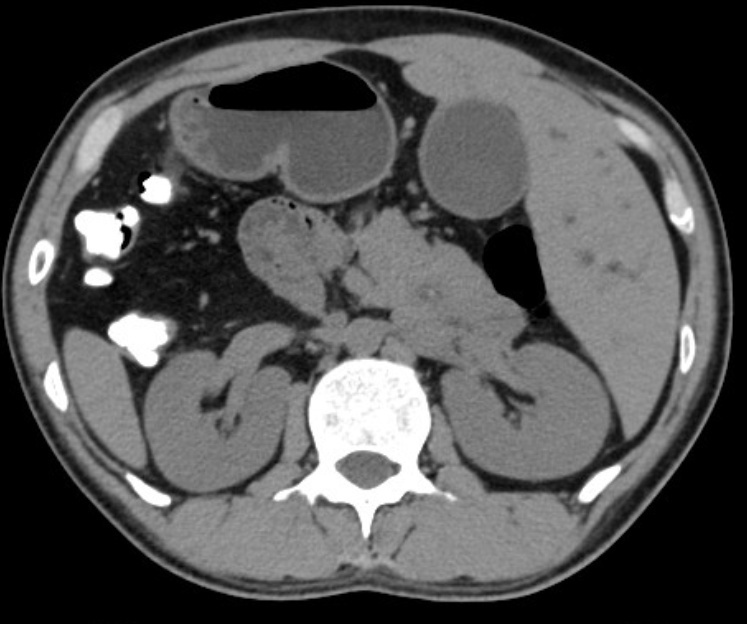

图片

反转的脏器CT影像